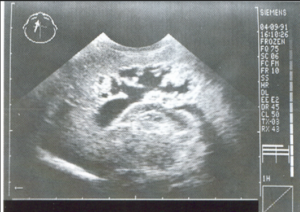

A 3-year-old child is admitted to the hospital due to decreased appetite and weight loss. She has been afebrile, and has not had vomiting or diarrhea.

Her activity level has decreased over the past two weeks.

She had been healthy until 2 months ago, when she was hospitalized for 48 ...

infection with mild respiratory distress and poor fluid intake.